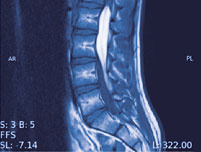

Mrt Der Lendenwirbelsaule